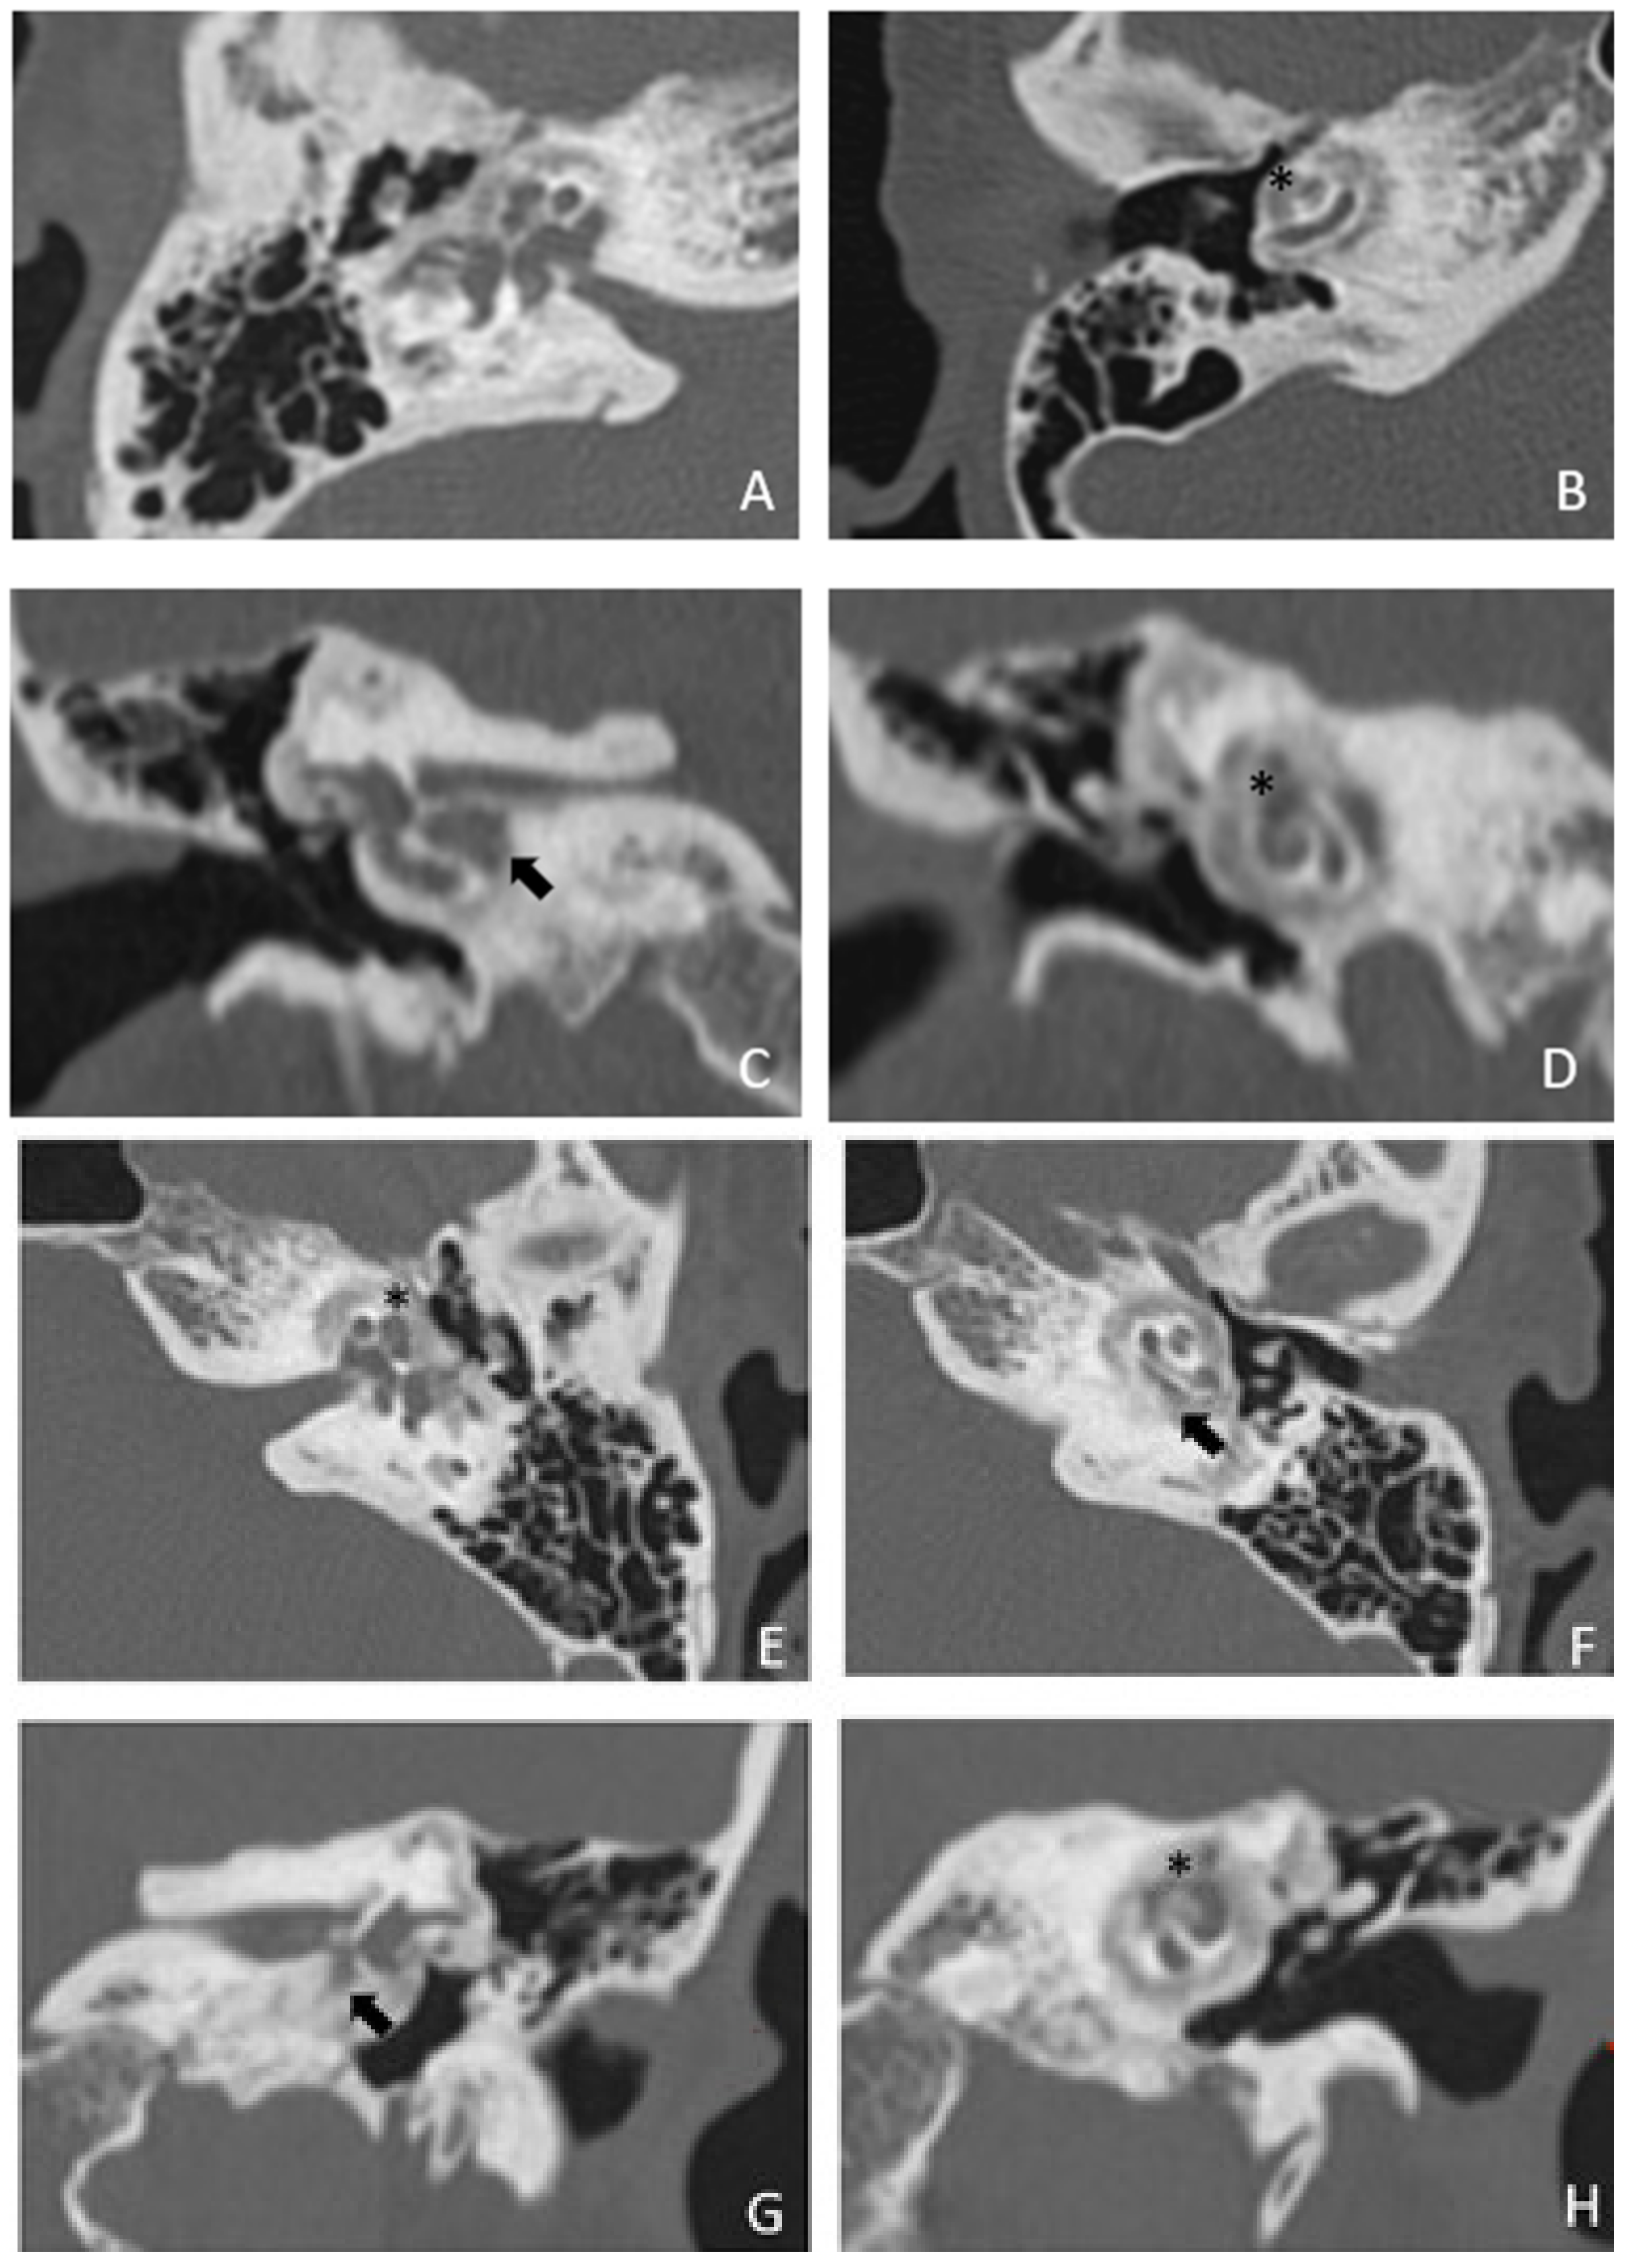

Patient #2, affected by OI-type I (COL1A1 mutation). MHL since diagnosis. Bone threshold was similar in both ears, but PTA was worse in the right ear with a larger ABG. HL progressed, but the difference between the two sides was maintained. The patient was fitted with conventional hearing aids bilaterally. Stapes surgery was not performed because of the radiological aspect (Figure 3 and Figure 4): a large cavity is present bilaterally and diffused communication between the cavity and the cochlea is evident.

Figure 4. MR images of patient #2 with osteogenesis imperfecta. MR cisternography: (A), axial plane; (B), coronal plane. Note the fluid-signal in the newly formed cavities (white asterisk).